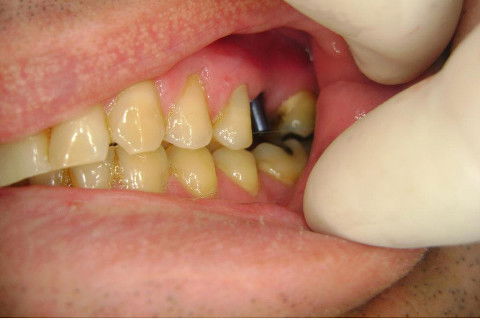

Instalação de um implante em região do 26. Utilizamos um implante cone morse Alvim Neodent 4.3 X 11,5. Foi uma cirurgia muito rápída e minimamente traumática, sem retalho e sutura.

Fotos do caso